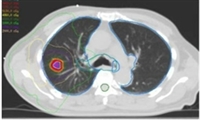

Stereotactic ablative radiotherapy - SABR

This is a specialised way of delivering radiotherapy using a small number of precisely targeted treatments to destroy tumours, whilst minimising damage to surrounding tissues. It is suited to patients with small primary cancers that haven't spread.

Our team use SABR to treat lung cancer patients.